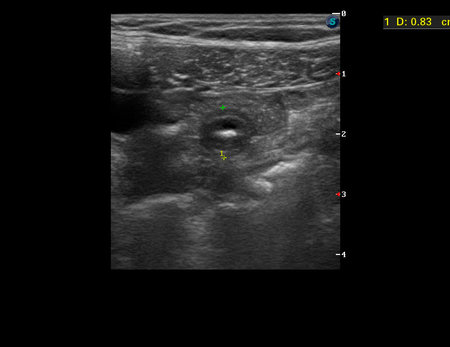

УЗИ - аппендикулярная колика, аппендиколиты

Мальчик 7 лет.

Боли в животе возникли 4 дня назад, продолжаются.

Температура нормальная. Анализы крови нормальные.

мезаденит и аскарида в просвете кишки

Пересмотрела видео еще раз. Все-таки я за инородное тело в просвете кишки.

Нет?Брехт писал(а):флегманозного то-же ведь нет

Есть. Смутила длительность заболевания и лабораторные данные.